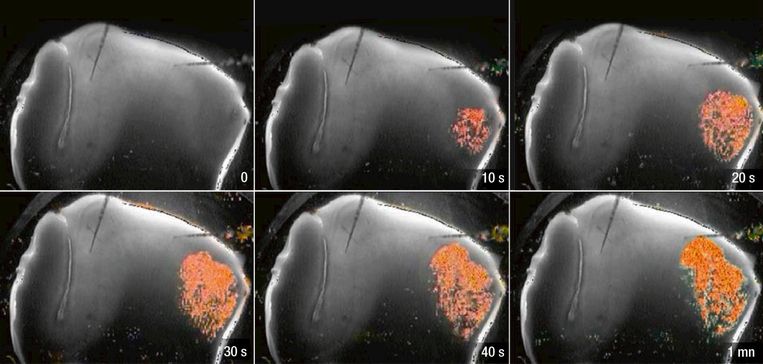

Door de stress komt er een kettingreactie op gang in de hersenen: een soort om zich heen grijpende brand. Uiteindelijk brengt die de dood en is er geen activiteit meer te zien. Beeld Science&Vie

Door de stress komt er een kettingreactie op gang in de hersenen: een soort om zich heen grijpende brand. Uiteindelijk brengt die de dood en is er geen activiteit meer te zien.Beeld Science&Vie

Uitgeputte neuronen

Het resultaat is verbluffend. Meteen na de laatste hartslag – op het moment dat de bloeddruk drastisch daalt – zie je hoe de neuronen in álle delen van de hersenen álle activiteit staken. Alsof ze zich bewust worden van het probleem, en zo min mogelijk energie willen verbruiken. Dit kan tot twee à drie minuten duren. Indien de bloedcirculatie dan opnieuw op gang zou komen, is er geen schade. Maar op een zeker moment raken er neuronen uitgeput: ze geven de strijd op. Ze lossen massaal kalium en glutamaat, een neurotransmitter. Dit brengt een kettingreactie op gang. Met een snelheid van 50 micrometer per seconde trekt die door de hersenen. Geen flash. Maar een voortschrijdende golf van warmte en energie. Een soort explosieve om zich heen grijpende brand die de eigenlijke dood met zich brengt. Want het kalium is giftig en doodt de neuronen.